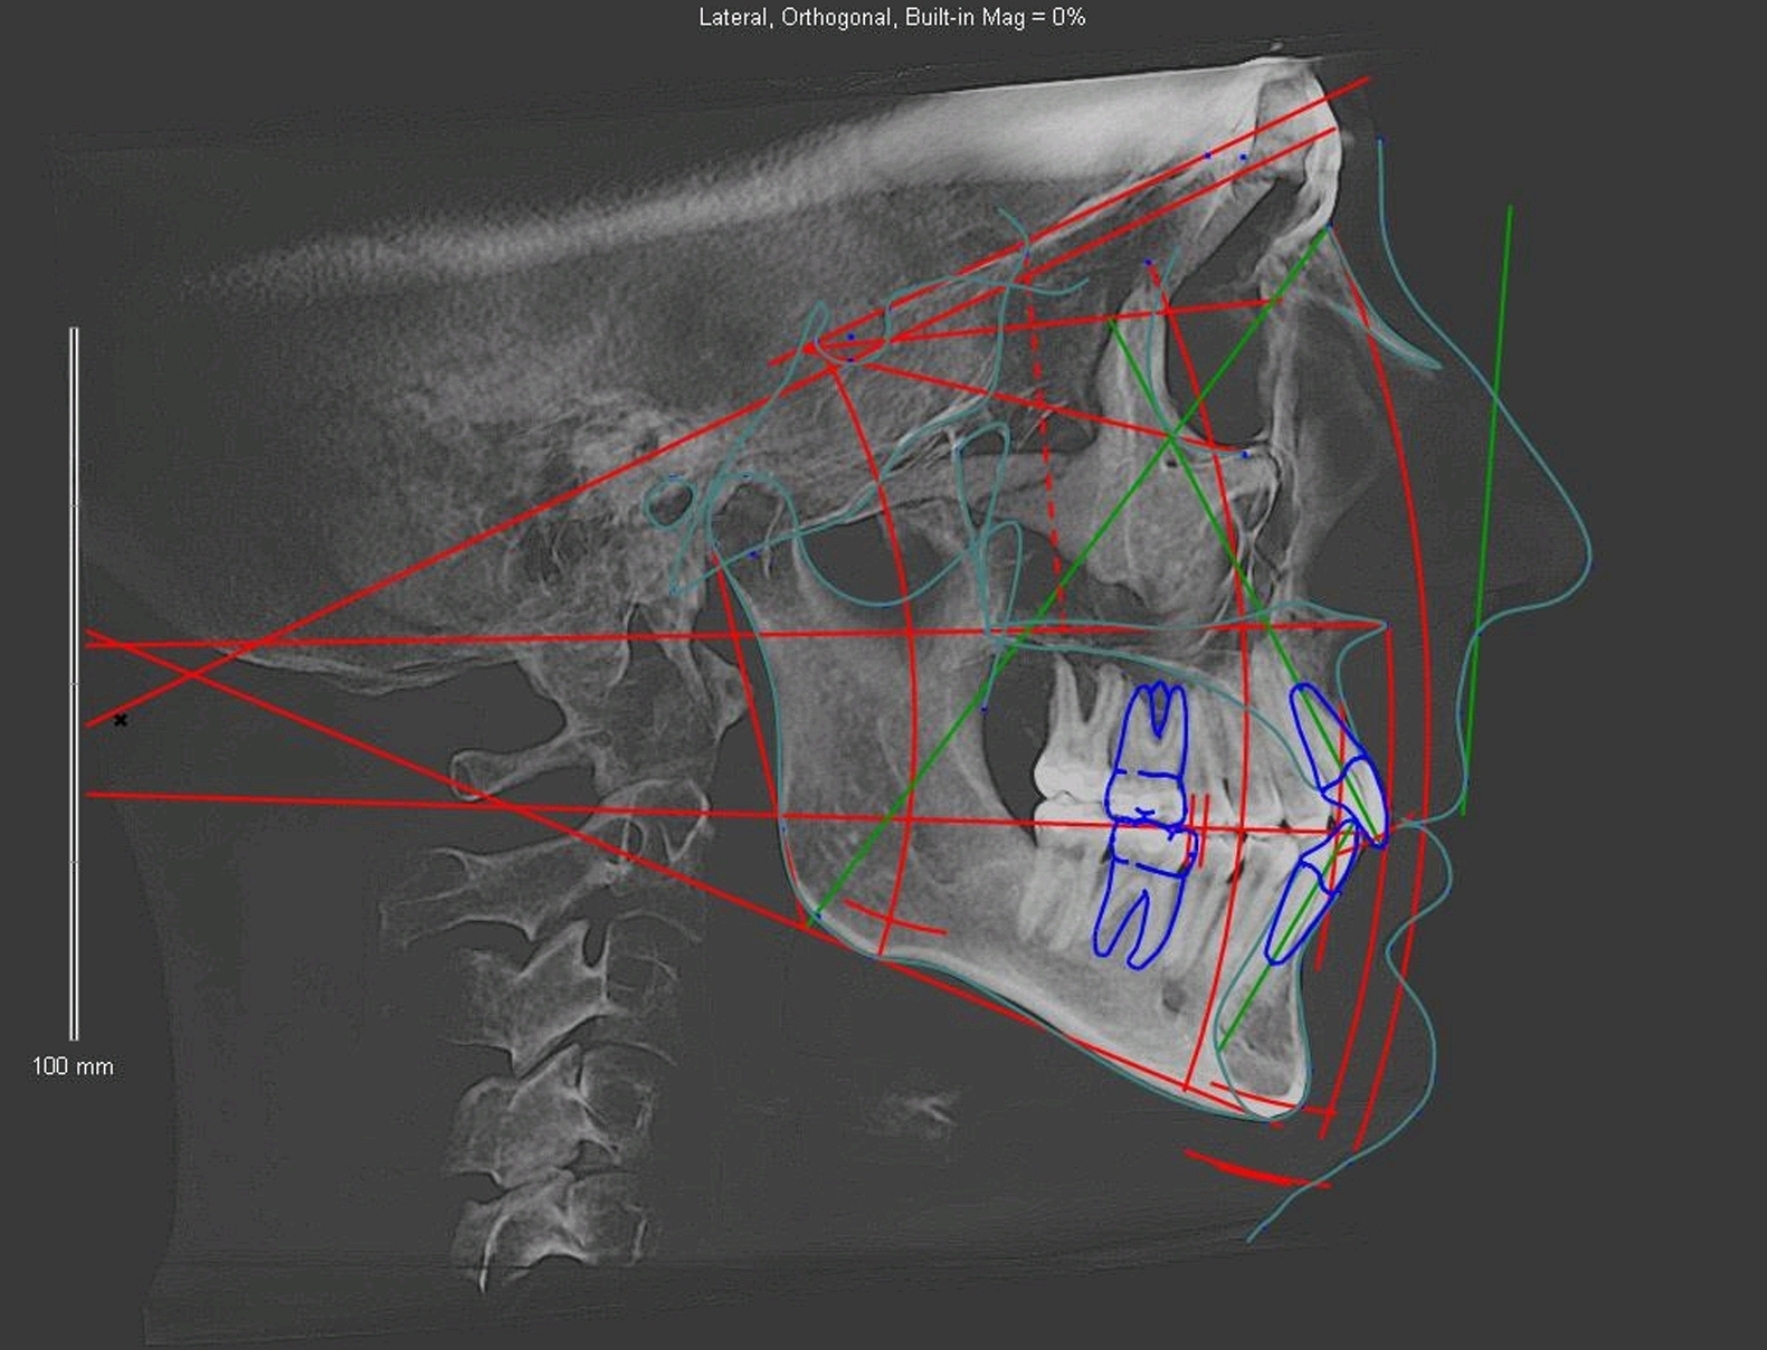

Я и сама пострадала от ортодонтического лечения, которое причинило вред не только моей внешности и самооценке, но и моему здоровью. Но все же женщины в первую очередь беспокоятся о своей внешности. На фото заставки к этой статье мы видим удивительно красивую девушку, у которой после брекетов лицо буквально осунулось, и, как она сама описывает на портале http://breket.info, все знакомые спрашивают ее при встрече, что с ней случилось, и не болеет ли она. Лицо этой пациентки все равно осталось красивым, но мы не можем не заметить, что у неё ушла миловидность овала лица, и будто ей прибавилось лет. О таких вещах в обсуждении на одном из форумов легендарный А.О. Савинов сказал очень точно — во многих случаях после брекетов молодые пациентки с милыми щёчками получают на выходе «старушечьи личики». Доктор Гиббс из США собирал информацию о таких случаях в течение сорока (!) лет, что стало делом его жизни. Все его исследования указывают на то, что и так ясно, как белый день — брекеты удлиняют лицо, способствуя его вертикальному росту. При этом общепризнанным фактом сегодня является то, что долгосрочный успех ортодонтического лечения зависит от направления роста лица, и что так называемые forward growing (горизонтально развитые) лица выглядят лучше.

На представленных выше фото двух девушек мы видим огромную разницу в расположении их верхней челюсти — так называемой maxilla, и то, как она влияет на красоту лица. У девушки слева верхняя челюсть выдвинута вперёд, в то время как у девушки справа она вытянута вниз. Причина такого различия, по утверждению знаменитого основателя системы orthotropics (горизонтального роста лица), доктора Джона Мью, кроется не в генетике, а в искажающем структуру роста лица неблагоприятном воздействии окружающей среды (отсутствие или недостаток грудного вскармливания, при котором недостаточно развиваются лицевые структуры, родовая травма, сосание пальца или соски, недостаточное количество твёрдой пищи, некачественное ортодонтическое лечение). Девушка слева выросла в благоприятных для развития лица условиях, в то время, как пациентке справа не так повезло и, более того, она прошла через лечение на брекет-системе. И количество людей, подвергающихся такому неблагоприятному вертикальному росту лица, неуклонно растёт.

Внутриротовые устройства для горизонтального роста лица начали разрабатываться в Европе и Америке ещё с начала двадцатого столетия, и получили особое развитие в восьмидесятые-девяностые годы, когда свет увидели самые известные на сегодня внутриротовые аппараты для расширения верхней челюсти Bioblock и ALF. Эти исследования на 180 градусов переворачивают все те представления, которым сегодня обучают стоматологов и ортодонтов, но, какой-то причине не получают повсеместного распространения, хотя преимущества этого метода более чем очевидны. Наиболее показательным случаем в этом отношении является история двух близнецов, чьё фото представлено выше. До ортодонтического лечения они выглядели практически одинаково, но первый прошёл лечение на брекетах с удалением скученных зубов, а второй — на расширяющем челюсти внутриротовом аппарате без удаления зубов (по методике orthotropics). Ортотропы выдвинули верхнюю челюсть, в то время как традиционная ортодонтия задвинула ее назад и вытянула вниз. Ещё раз обратите внимание на линию скул и подбородка по отношению к носу!

Попробуйте погуглить лица моделей в профиль, и вы увидите, что у всех этих красивых людей горизонтально выдвинутая вперёд верхняя челюсть. Брекеты же приводят к вертикальному вытягиванию максилл. Этому способствует множество факторов, но, если описать проблему простыми словами, то выглядит это так: дуга брекетов оказывает равномерное воздействие одновременно на все зубы. Какие из них выиграют это «перетягивание каната»? Это будут большие коренные зубы с более развитыми корнями. Именно по этой причине кости лица на брекетах оттягиваются назад, а зубные дуги сужаются. Зубы при этом действительно становятся ровными, но, увы, улыбка становится узкой и совсем не ослепительной — той, на которую мы надеялись. Средняя часть лица при этом удлиняется и становится более плоской, и развитие лица происходит совсем не в том направлении, как у моделей…

Ортотропы отличаются от обычных ортодонтов тем, что выравнивают зубы именно расширением зубных дуг (при помощи устройства Bioblock). Справляясь с основной «зубной» проблемой, они способствуют горизонтальному развитию лица, что улучшает его после лечения. Единственная проблема в том, что этот метод доступен, в основном, для детей в возрасте 8-12 лет. Но не все потеряно и для взрослых, которые прошли лечение традиционными брекетами и обнаружили, что их лицо было разрушено, или для тех взрослых, кто хочет выпрямить свои зубы и достичь большей гармонии лица. Эти цели у взрослого человека достигаются либо методикой мьюинга (но при этом у вас не должно быть удаленных под брекеты зубов со стянутым брекет-системой пространством, и ниже вы видите один из таких примеров на курсе гармонизации пропорций лица , где применяются дополнительные остеопатические пальцевые техники):